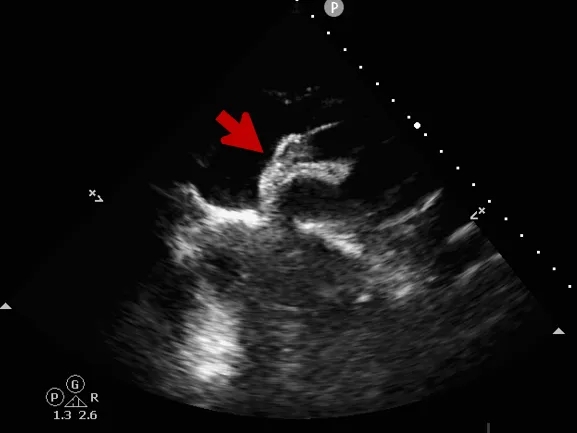

术前超声

超声描述:右房室较大,左房室不大。房间隔中部可见中断,约14x16mm。缺损边缘较硬,二尖瓣侧缘、后上缘分别为16mm、8mm,主动脉侧缘、后壁缘分别为0mm、10.7mm,上、下腔静脉侧缘分别为16、14mm。十字交叉存在。房间隔长度43mm。M型二尖瓣呈双峰,前后叶逆向,E-E间距相等。

CDFI:房水平可见一股红色彩流由左房经缺口进入右房。主动脉瓣下左室流出道探及微量舒张期反流信号。三尖瓣口右房侧探及微量收缩期反流信号,Vp 2.7m/s,PG 29mmHg。二尖瓣口左房侧探及微量收缩期反流信号。

术中复测

超声可见房间隔连续中断,彩色多普勒可见过隔血流

测量房间隔缺损直径最大为23.9mm,房间隔总长53.8mm